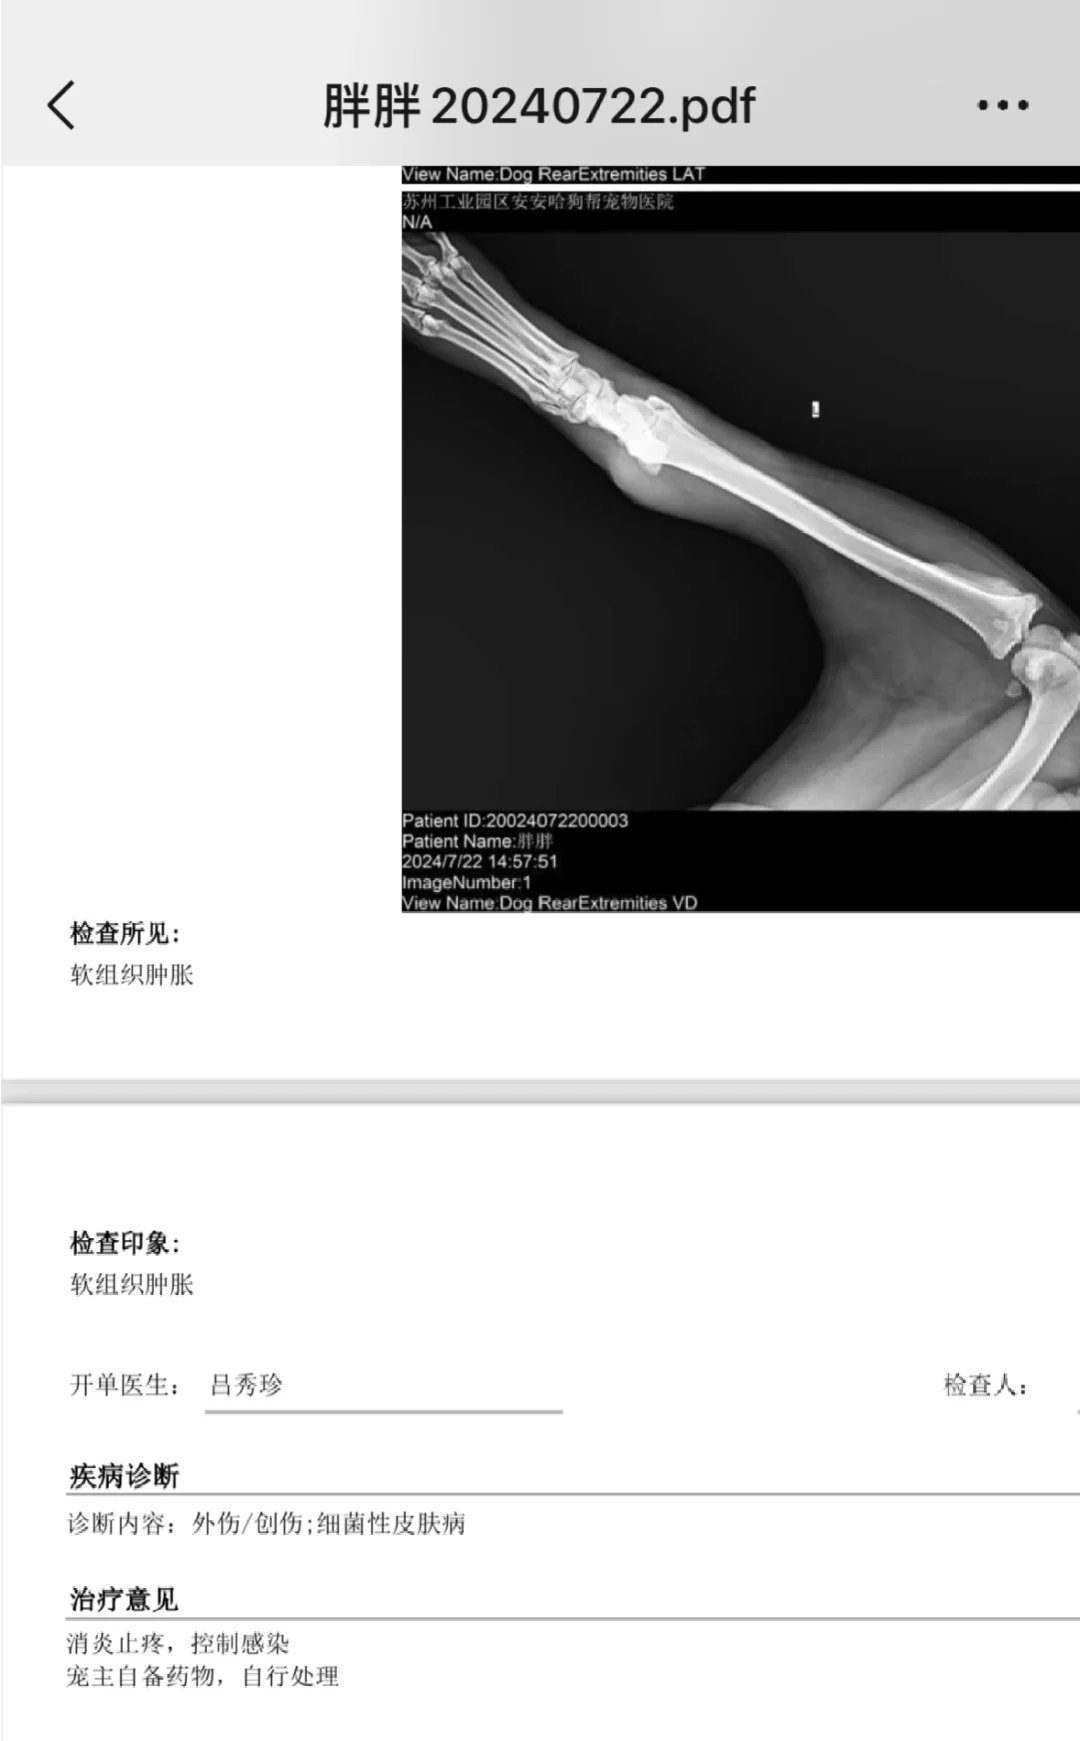

阿拉斯加 苏州 我家宠物好可爱 话是21号说的,身价是22号提升的,检查➕买药花了3000!! 胖墩:让你说我不要钱,该!